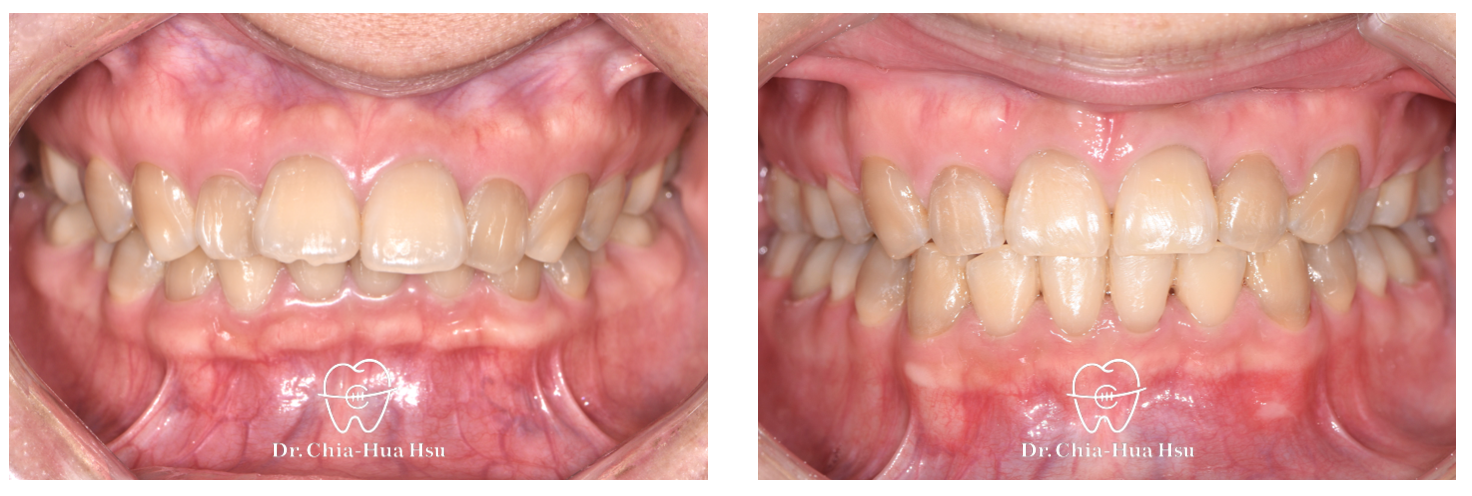

• 矯正過程:患者因為有深咬的問題,使用「輔助線」來改善深咬。

• 矯正小知識:這裡的「輔助線」為『壓低弓線 (intrusive arch)』。intrusive arch放置在大臼齒的矯正器,並與前牙主要弓線相連,利用大臼齒(後)當支點對下顎門牙(前)提供向下的力量,而大臼齒本身會受到反作用力向上,這兩種牙齒移動都有助於改善深咬!

治療前

治療後